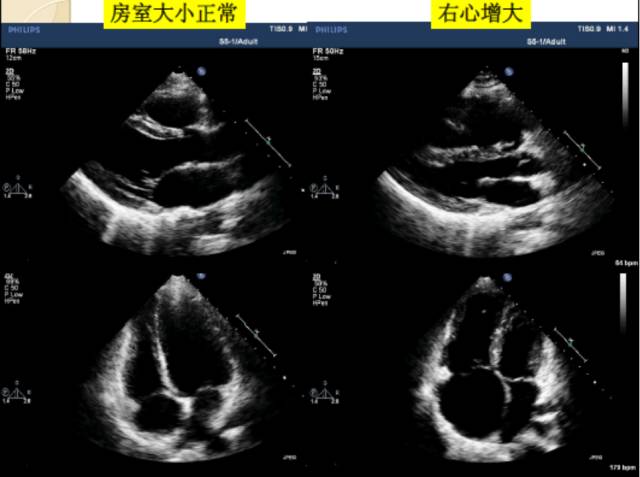

4、右心室大小的评估

由于右心室的几何构型复杂、定量评估困难,目前临床上多采用右心室的面积或内径与左心室对比来作出定性评价。

5、右心室舒张末期面积

右心室的大小(与左心室二维面积比较)